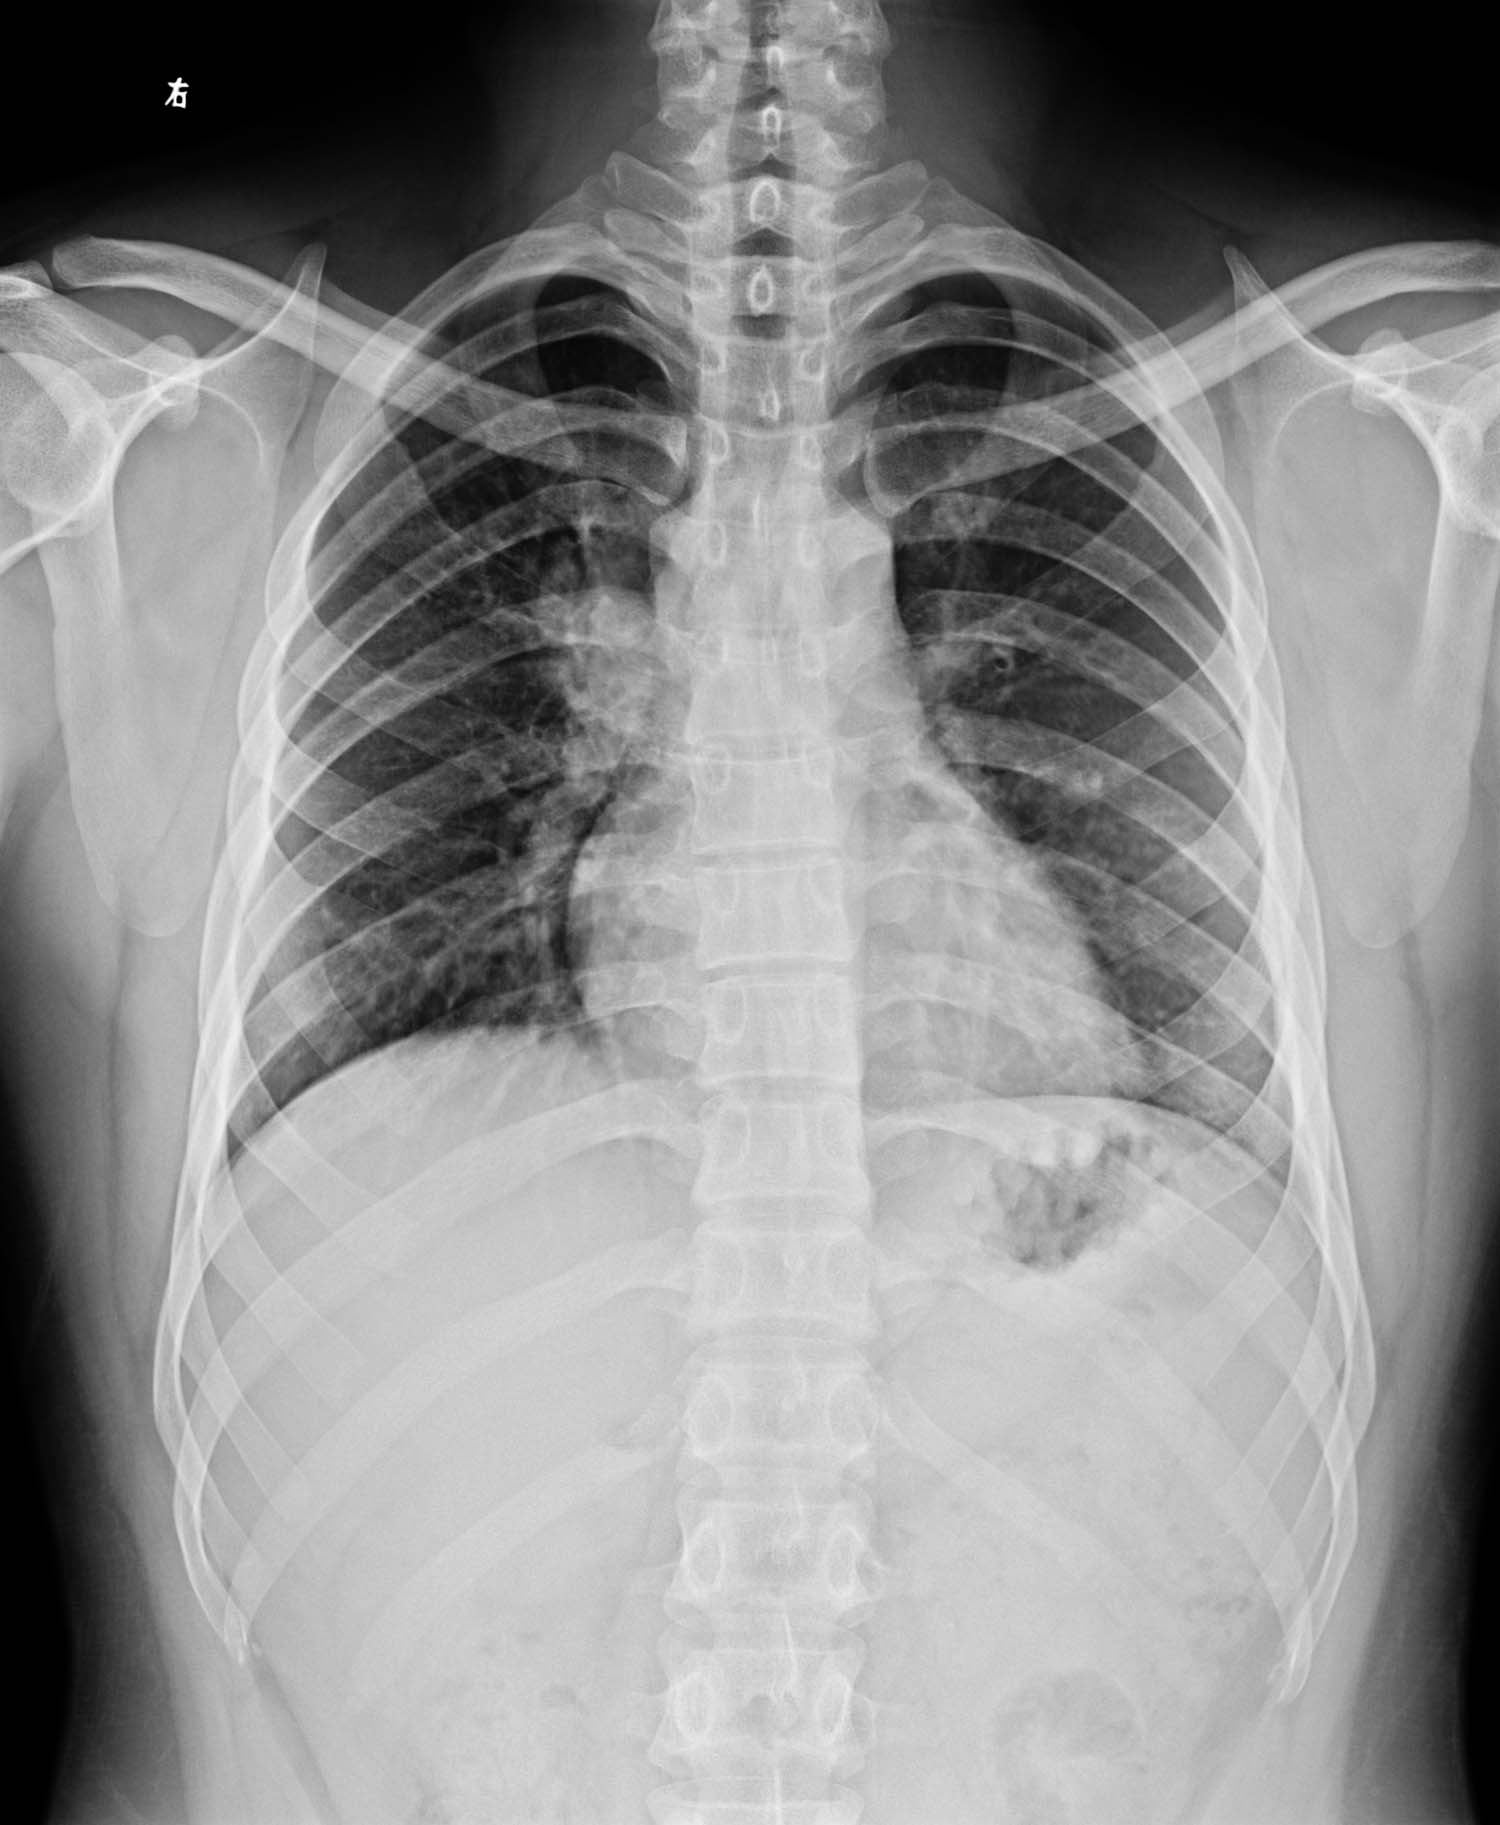

标题: X1894:[讨论]男,26岁,发热右上肺阴影性质 [打印本页]

男,26岁,发热

侧位片未见明显异常,右肺门旁影暂考虑右6后肋,右2前肋前端,局部肺纹理及右上肺动脉所至重叠影,必要时ct检查排除其它。另双肺纹理稍多,考虑支气管疾患,不知有否类似症状?

右肺门上方阴影性质?男,二十多岁,有发热

右上肺门似肿大淋巴结,考虑结核,建议做ct

正位示右肺门类圆形肿块影,侧位未见显示,建议ct进一步检查.

结合年龄考虑:原发型肺结核可能,还是做个ct更精确,毕竟恻位片上没见到。

有肺门处阴影,侧位未见其影。考虑血管影

右肺门角消失;做ct